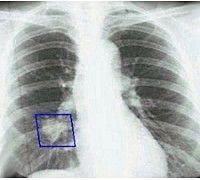

Рак лёгкого — это злокачественное новообразование!

На фото — рак легкого реального человека. Рак лёгкого — это злокачественное новообразование, которое возникает из клеток эпителия бронхов, бронхиол или легочной паренхимы. Это одно из наиболее распространённых онкологических заболеваний […]